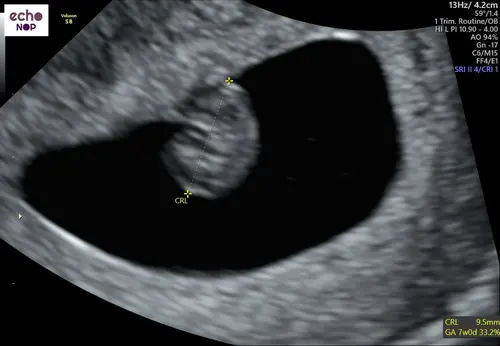

Nu 9+1, nog steeds alles helemaal in orde met allebei 😍🙏🏼🙏🏼